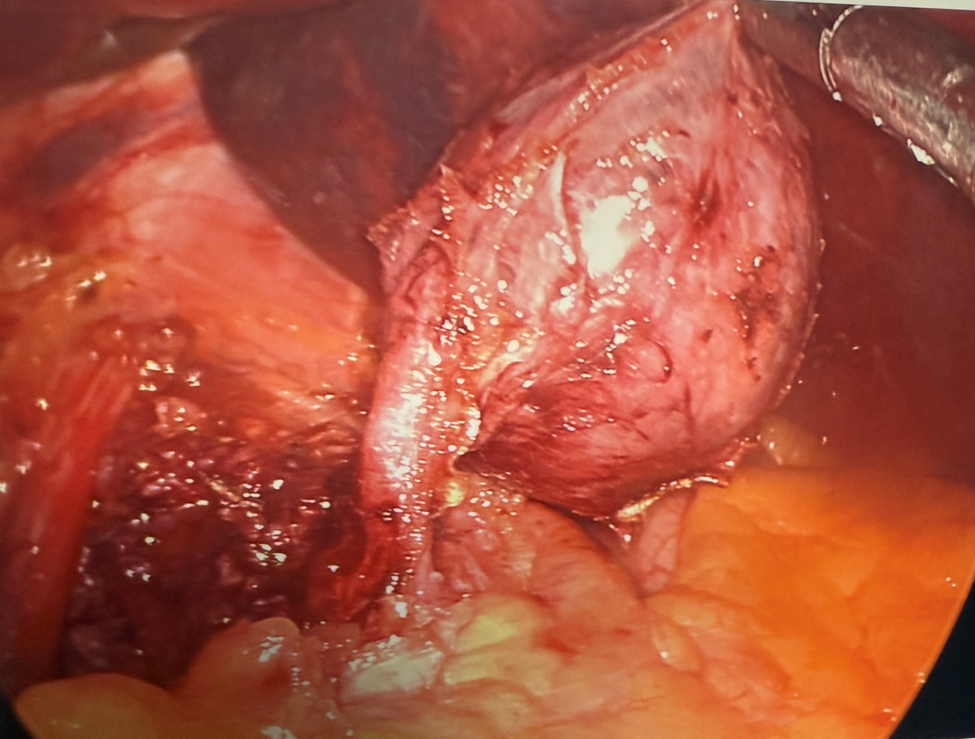

A 28-year-old healthy gentleman with no prior medical history presented to the emergency room with sudden onset of severe right upper quadrant and epigastric abdominal pain associated with nausea and vomiting. Liver enzymes and lipase were normal. CBC showed mild leukocytosis (12.24 K/microL).  Cross-sectional imaging revealed a well-circumscribed soft density lesion adjacent to the gastroesophageal junction (Fig. 1). Ultrasound evaluation did not show any cholecystitis or gall stones. Esophagogastrostomy did not show significant changes in the esophagus or in the gastroesophageal junction or in the stomach. Endoscopic ultrasound evaluation showed a well encapsulated lesion measuring 3 cm not arising from the muscularis propria of the esophagus but close to the GE junction with both liquid and solid contents (Fig. 2). Needle aspiration showed mucinous material suggesting possible esophageal duplication cyst.  Laparoscopy was performed ,revealing a pedunculated  cystic lesion at the gastroesophageal junction (Fig. 3). It was stapled at its origin, with a bougie in the esophagus to minimize the risk of narrowing the esophageal lumen (Fig. 3). Histopathological examination confirmed it was indeed an esophageal duplication cyst (Fig. 4,5 &6). The inner lining of the cyst was ciliated columnar epithelium (Fig. 4). Interestingly double layer of smooth muscle was noted (Fig. 6). Following surgical removal, the pain completely resolved and on follow up the patient was feeling completely normal.

Figure 3. Laparoscopic removal of the esophageal duplication cyst